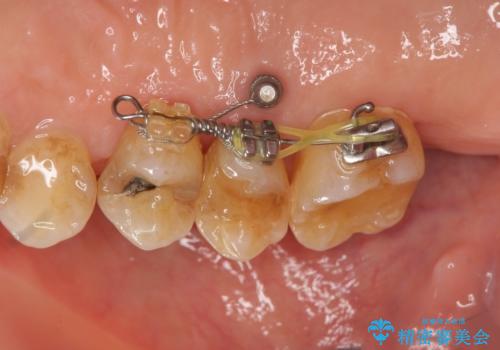

部分矯正を含む 歯周病治療 (再生治療・歯周ポケット除去・MTM・連結補綴)

検査の結果、強い歯ぎしりによる歯の周囲の骨の吸収が認められたため歯槽骨の再生・歯周ポケットの除去・力に対抗する連結補綴・補綴前処置としての小矯正を計画します。

今回連結補綴を行うにあたり、歯周病の問題を解決するために再生療法・歯周ポケット除去手術を、またより歯の神経を保存し力に対抗できる環境を整えるために小矯正を行い精度の高いメタルボンドクラウンを製作することができました。